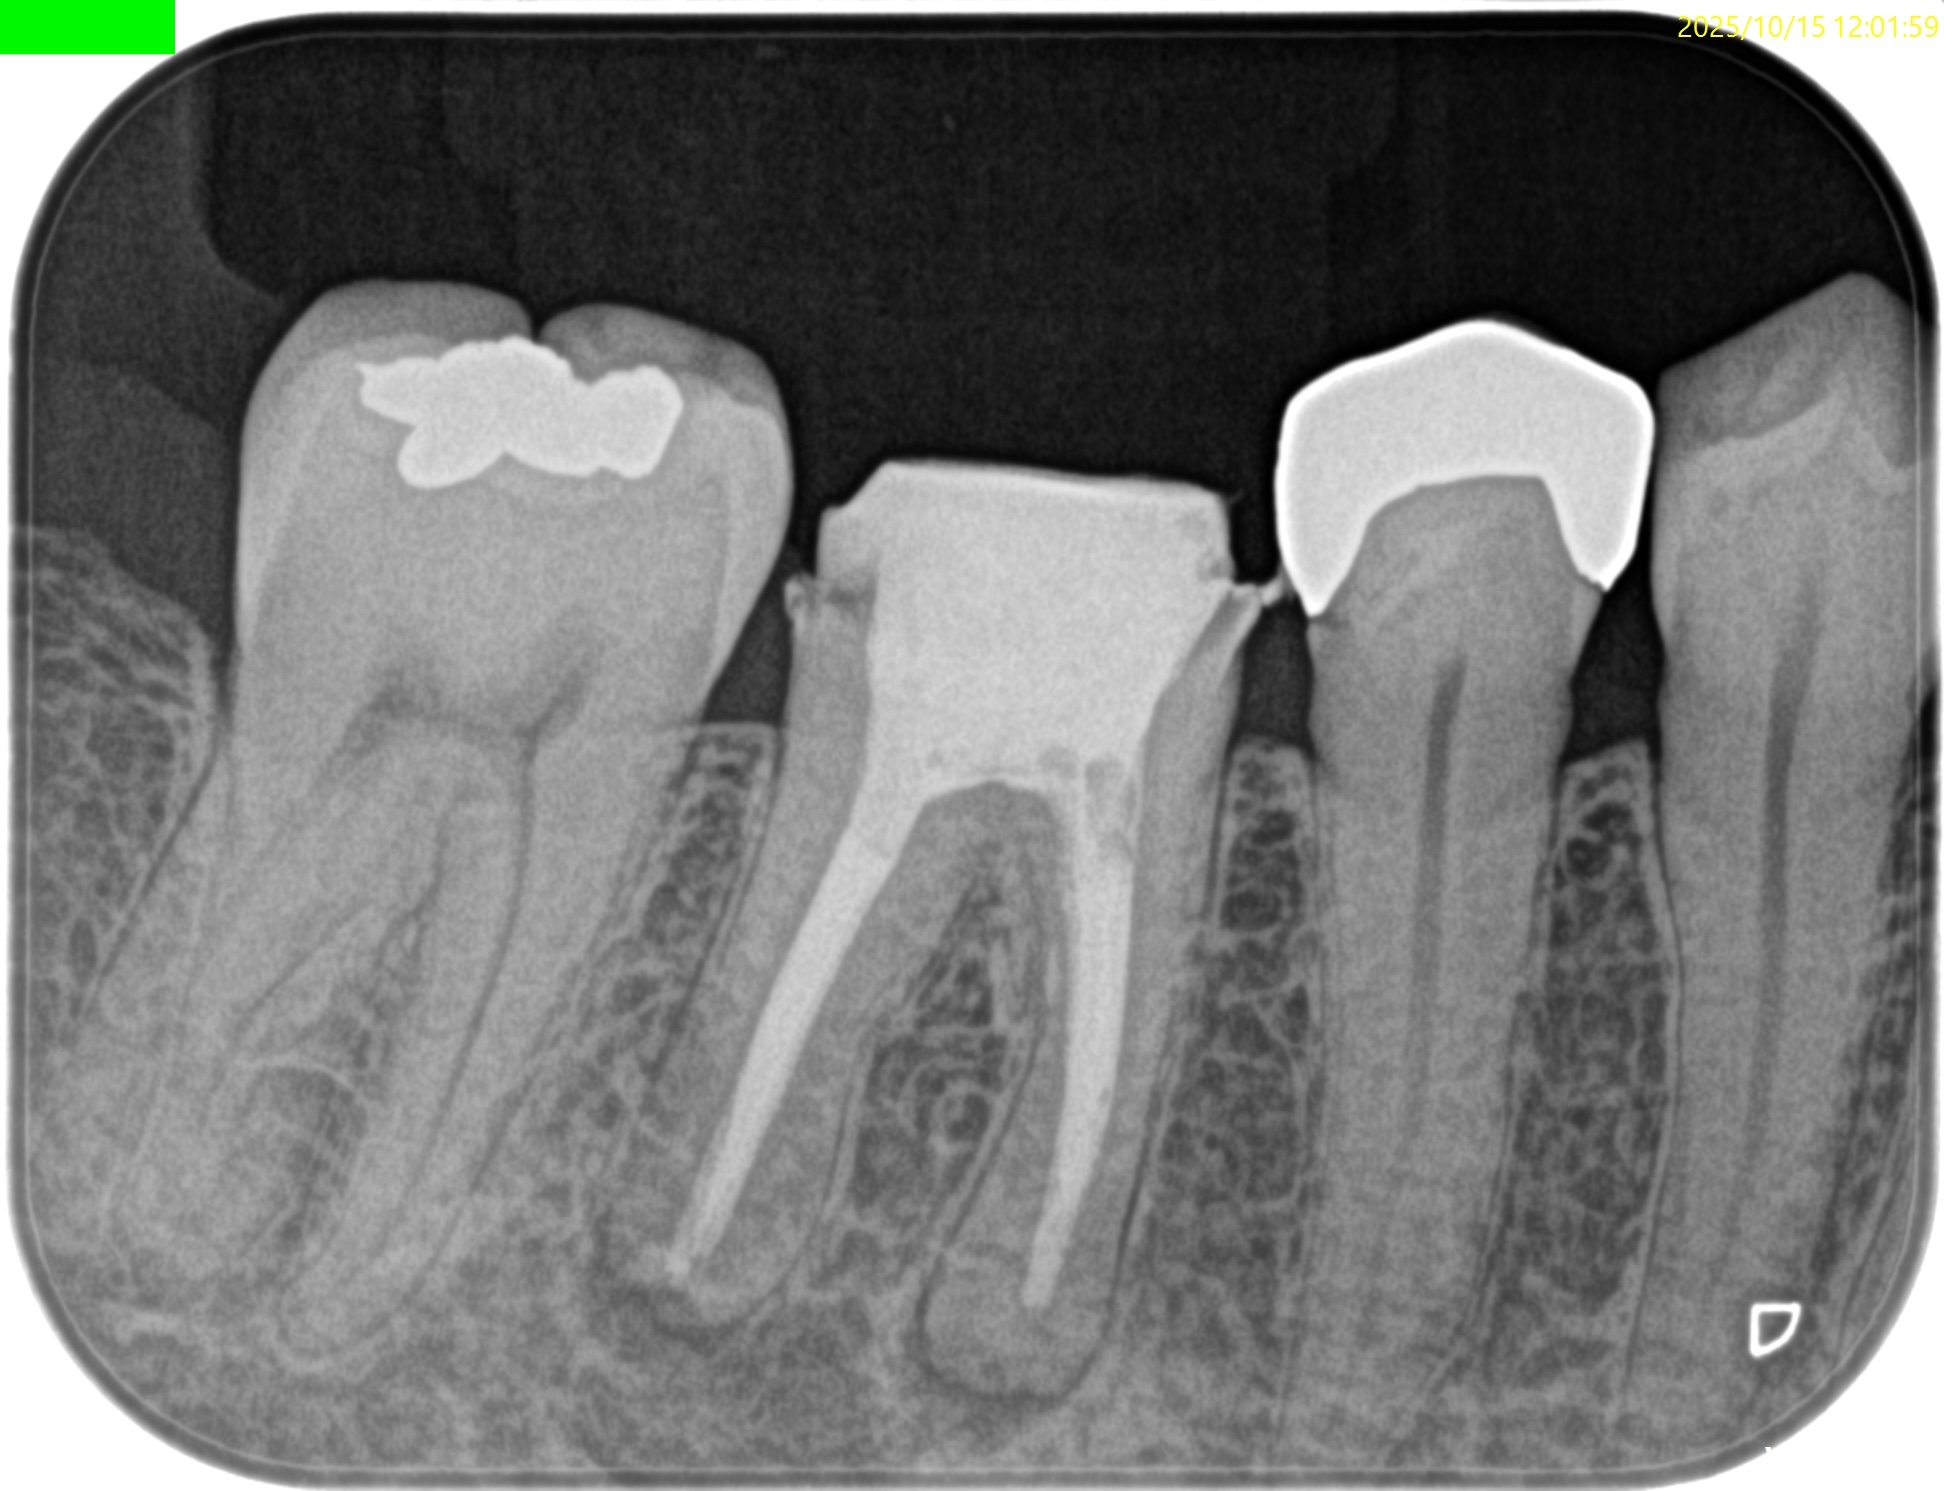

術後にPA, CBCTを撮影した。

M

D

縫合して終了した。

次回は1年後である。